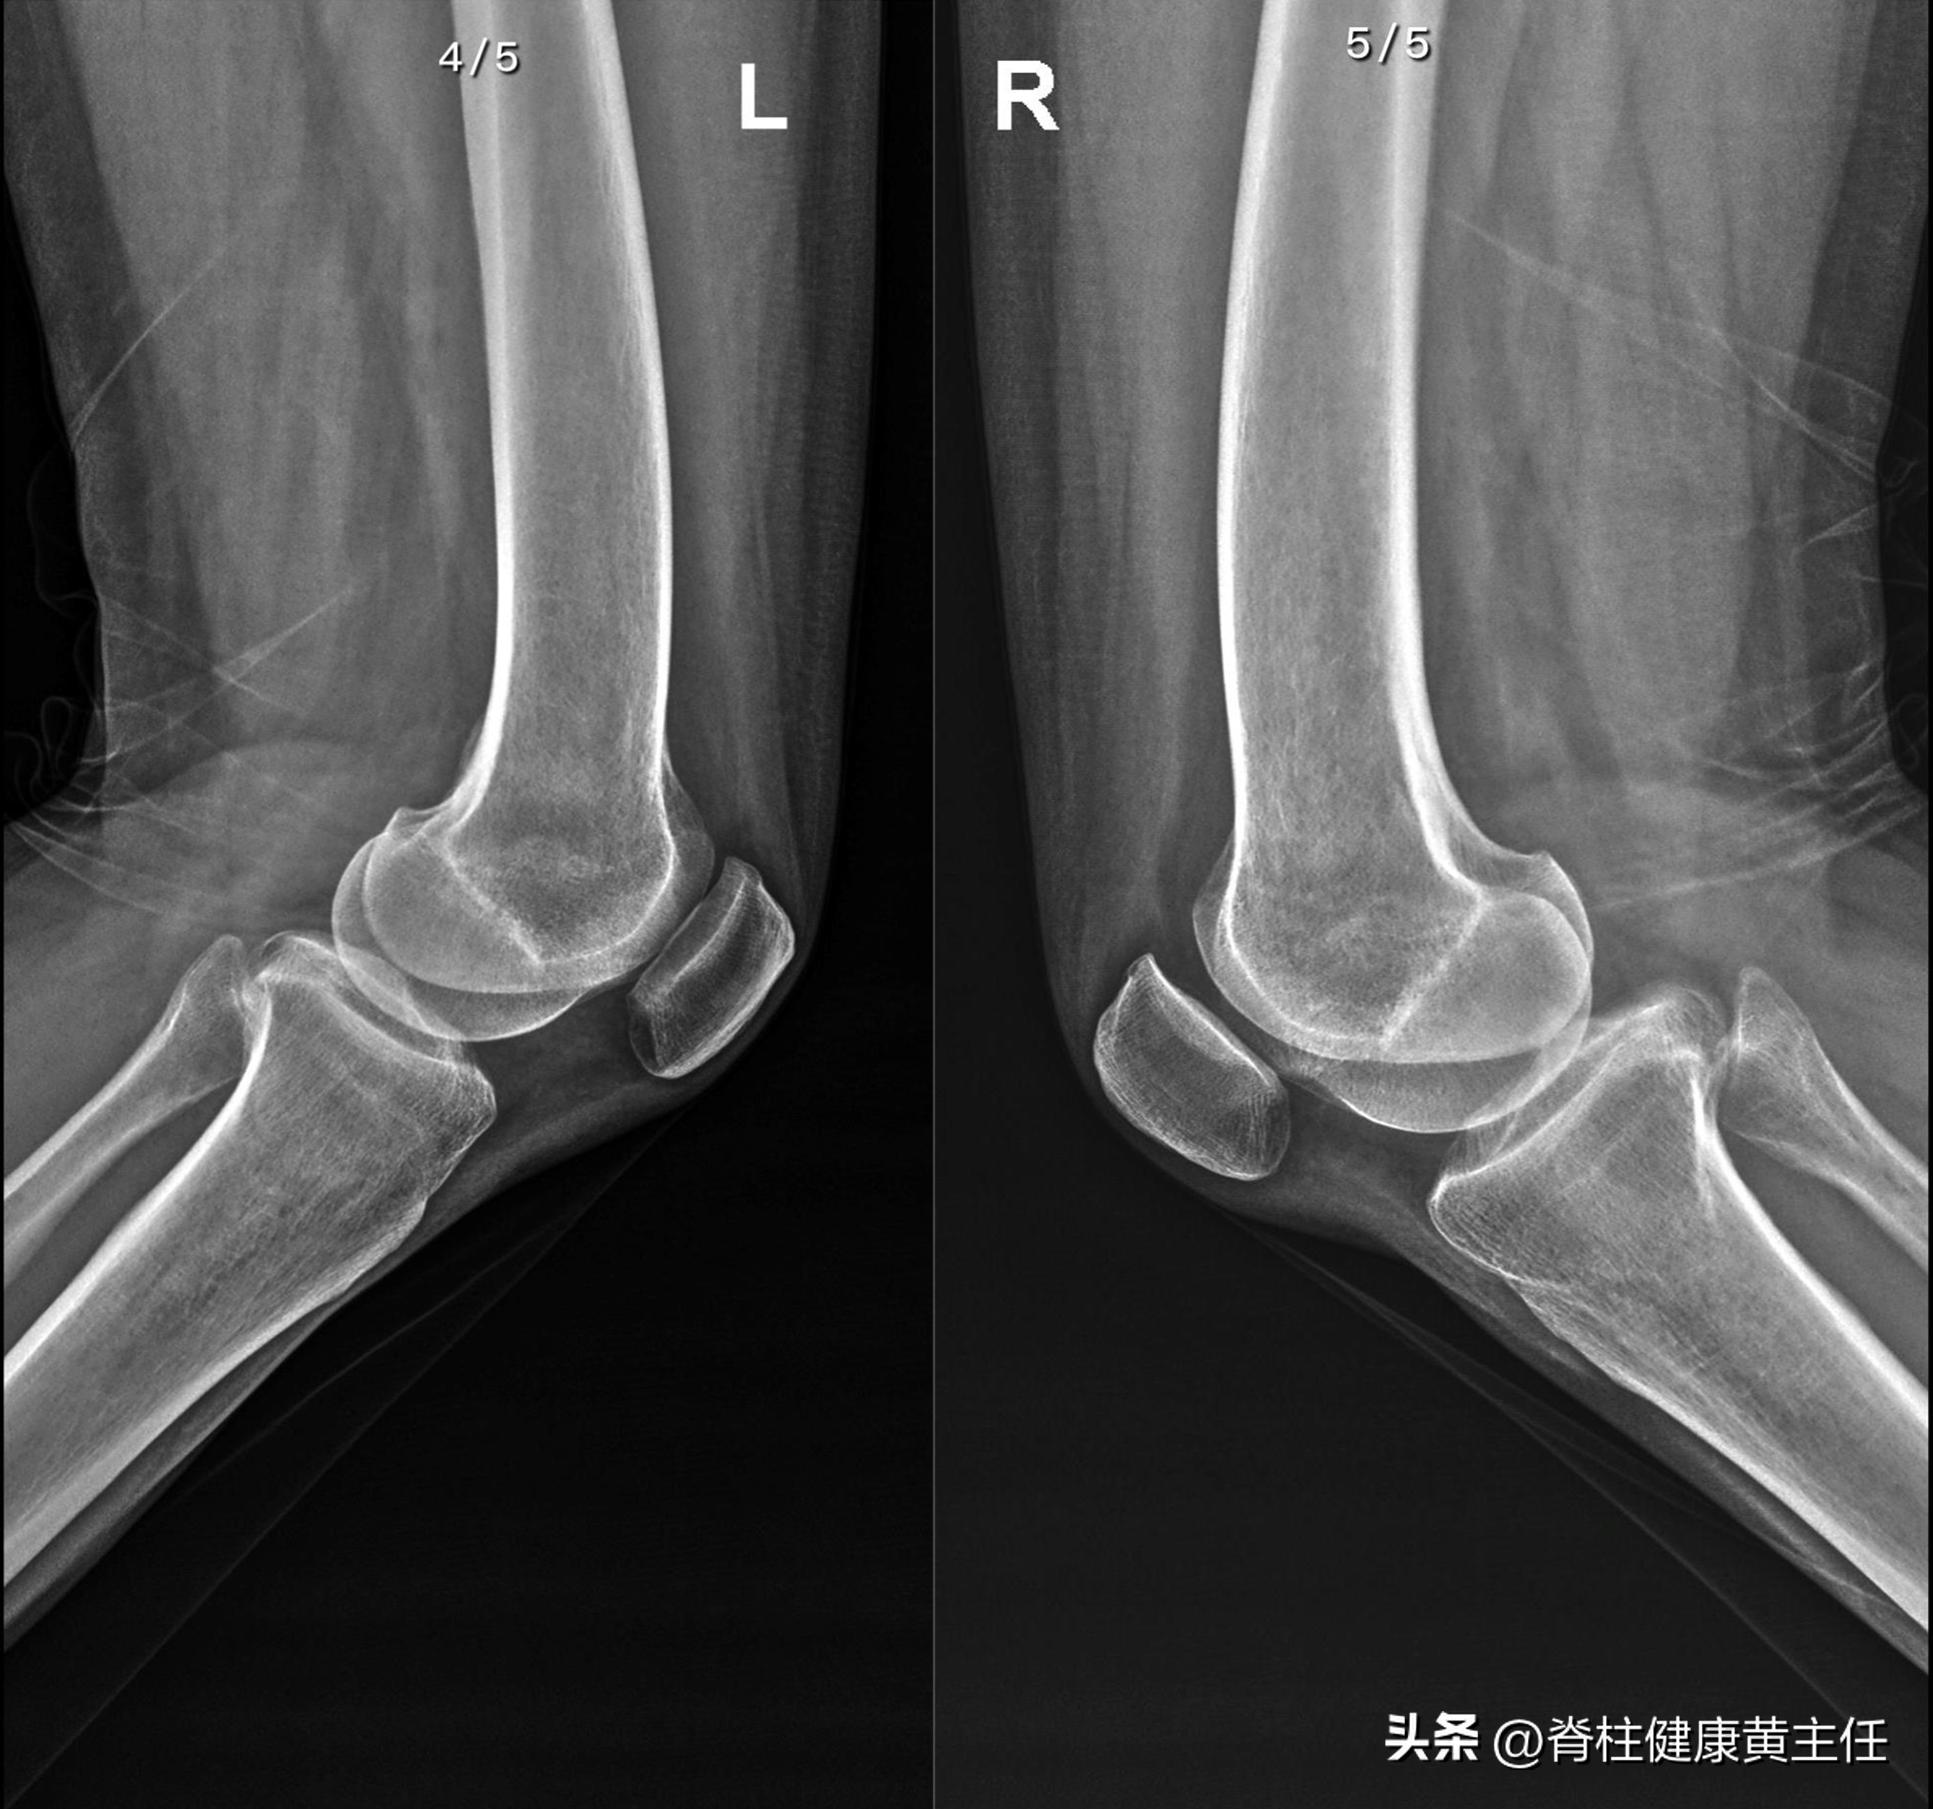

腰椎、双膝X光: 腰椎小关节不稳,腰椎退行性变,双侧膝关节未见明显骨质异常。

侧位片

因此,我们建议可再行MR排查软组织和半月板问题。